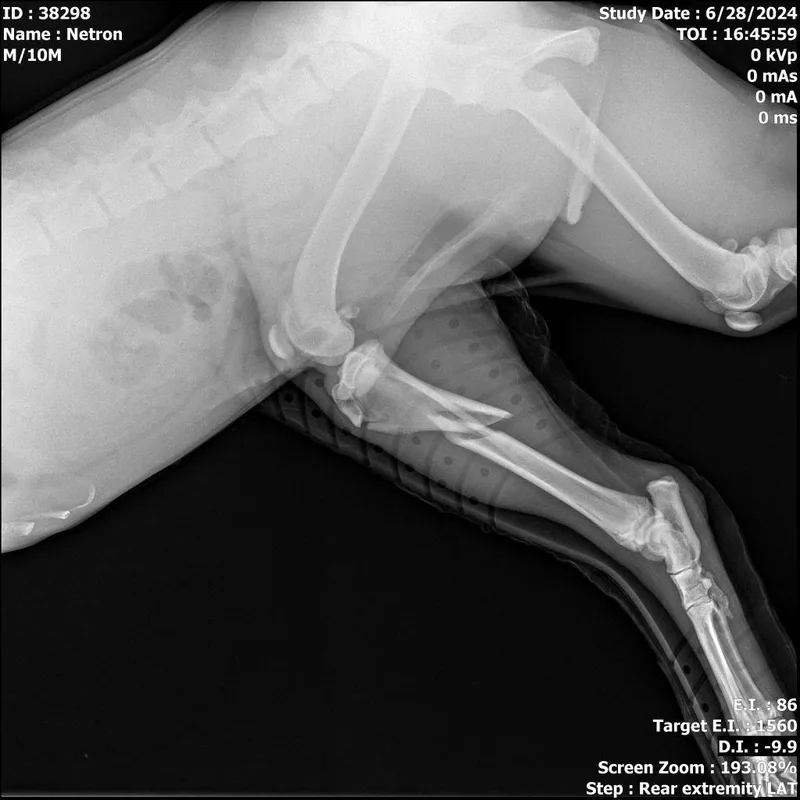

appears to have a displaced tibia fracture; this fx may be able to be set and splinted but will need to be set in alignment; x-rays have been reviewed by an off-site vet